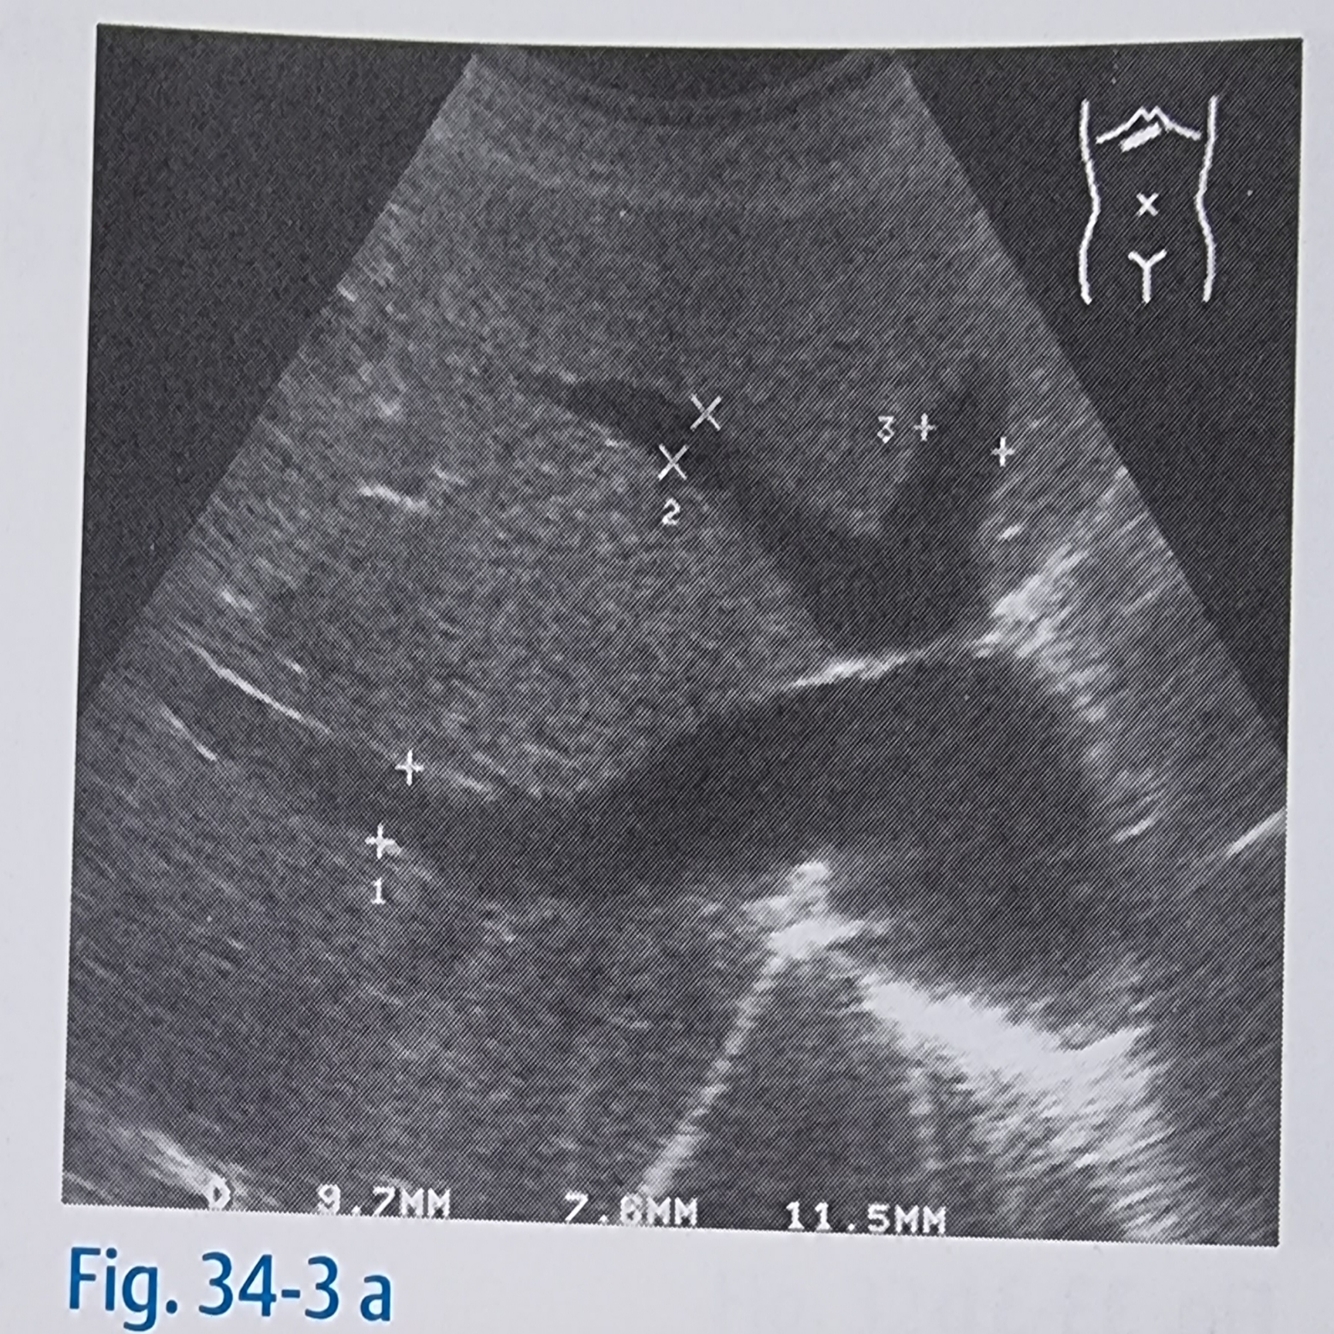

19

Q

Tumores hepáticos podem ser reconhecidos como?

A

Por sinais indiretos como o deslocamento em forma de arco das veias vizinhas

Veia hepática (10)

Tumor (54)